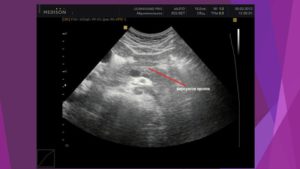

Но более информативным методом диагностики является ультразвуковое исследование. Одним из важных диагностических признаков в этом случае являются диффузные изменения железы. Контуры органа при этом могут быть неровными, а ее размеры, как правило, находятся в пределах нормы.

Фиброз поджелудочной железы не является самостоятельным заболеванием. Этим термином обозначают патологические изменения органа, которые обычно являются признаком хронического панкреатита. Фиброз определяется на УЗИ. Как правило, он не сопровождается симптомами, поэтому становится случайной находкой врачей при плановом обследовании пациента.

Клинических признаков фиброз не имеет. Его можно увидеть на УЗИ. Замещение паренхимы соединительной тканью видит патологоанатом при вскрытии больного. А вот определить фиброз по симптомам нельзя.

Важный метод диагностики фиброза поджелудочной железы – ультразвуковое исследование органов брюшной полости (УЗИ брюшной полости). Определяется диффузное повышение эхогенности органа, структура неоднородная, размеры уменьшены; возможно выявление расширения вирсунгова протока.

Более информативна эндоскопическая ультросонография, которая позволяет выявить линейные тяжистые включения разной протяженности и формы, бугристость контуров, гиперэхогенность паренхимы. При проведении ЭРХПГ выявляются изменения протокового аппарата, вызванные образованием рубцов.